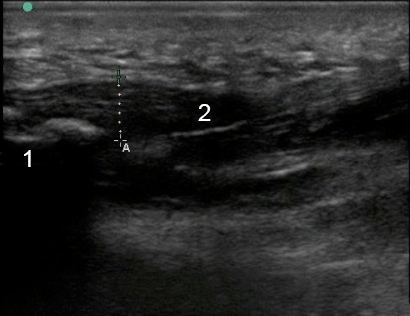

Foot & Ankle Plantar Fascia Image

Cancaneus

Plantar Fascia